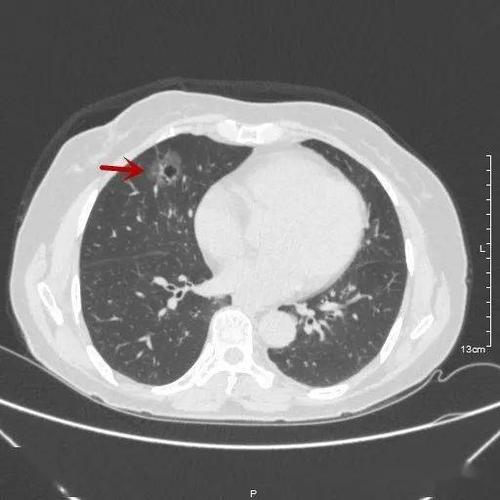

(右肺上叶中央型肺癌)

中央型肺癌的影像诊断

ct诊断中,哪些情况会被确诊为肺癌呢?

中心型肺癌ct图片

中心型肺癌